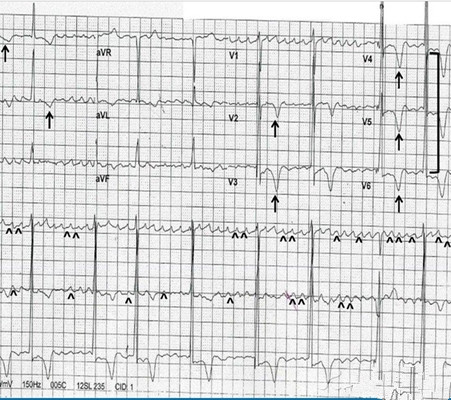

預激綜合徵心電圖 (79)

預激綜合徵心電圖 (8)

預激綜合徵心電圖 (80)

預激綜合徵心電圖 (81)